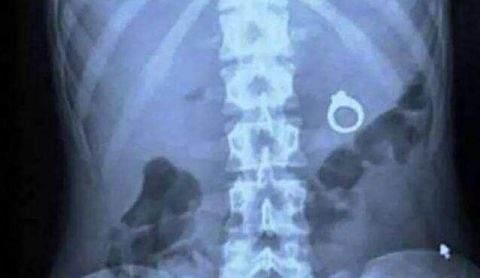

通常,医院通过X线检查来判断患者体内有没有异物,根据X检查把异物分为可显影异物和不可显影异物。

可显影异物:指在X检查中可以显示的异物,一般是一些密度较大的物品,比如:小铁丝、带金属的纽扣、硬币等等。